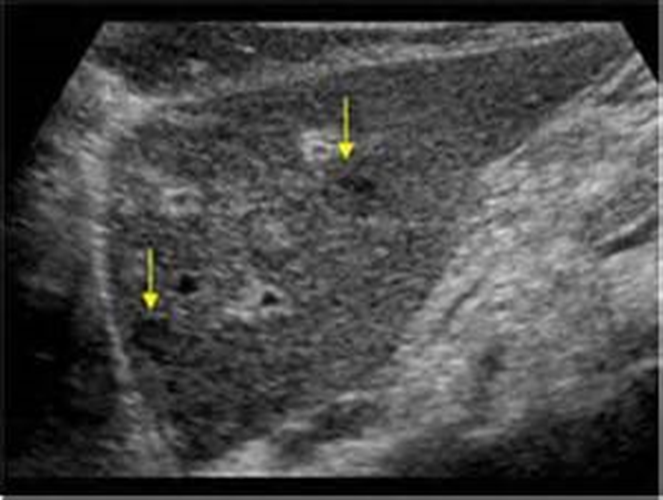

What is this image showing?

Distal Cholangiocarcinoma

Sclerosing Tumor